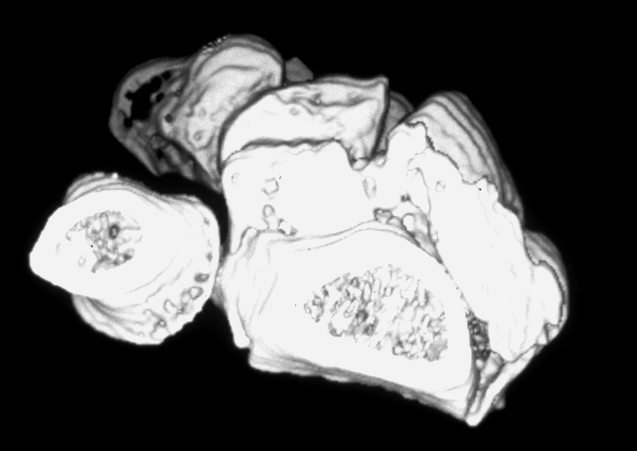

Case 3 CT

Case 4 CT

Case 8 CT